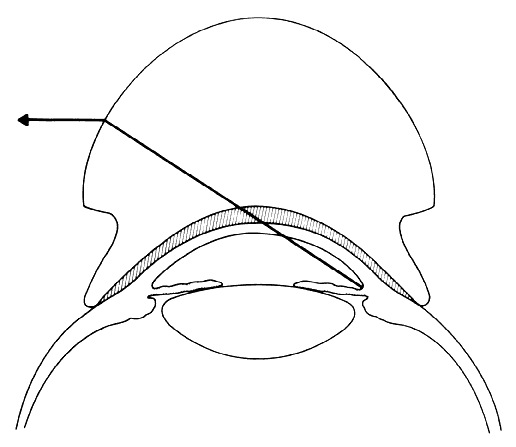

The use of goniolenses of this type (Koeppe) constitutes the direct method of gonioscopy. Since these goniolenses have a steeper curvature than the cornea, there is a space between the inner surface of the lens and the cornea, This space is filled with methylcellulose, saline, or some other solution. For all practical purposes this solution creates an optical continuity between the lens and the cornea (Fig. 3). The more steeply curved outer surface of the gonioscopy lens replaces the cornea-air interface, thus altering the critical angle and permitting visualization of the angle. The chamber angle is observed by viewing directly across the anterior chamber. A true image is seen with true spacial orientation. Magnifying loops, a hand-held microscope, or an operating microscope is used to magnify the image viewed (Fig. 4); the gonioscopy lens itself provides about 1.5 x magnification.

Fig 3. Schematic drawing of a direct gonioscopy lens. The steeper radius of curvature of the gonioscopy lens is substituted for that of the cornea, permitting direct visualization of the angle recess. Note the fluid bridge between the cornea and the gonioscopy lens, which links them functionally into a single optical system.